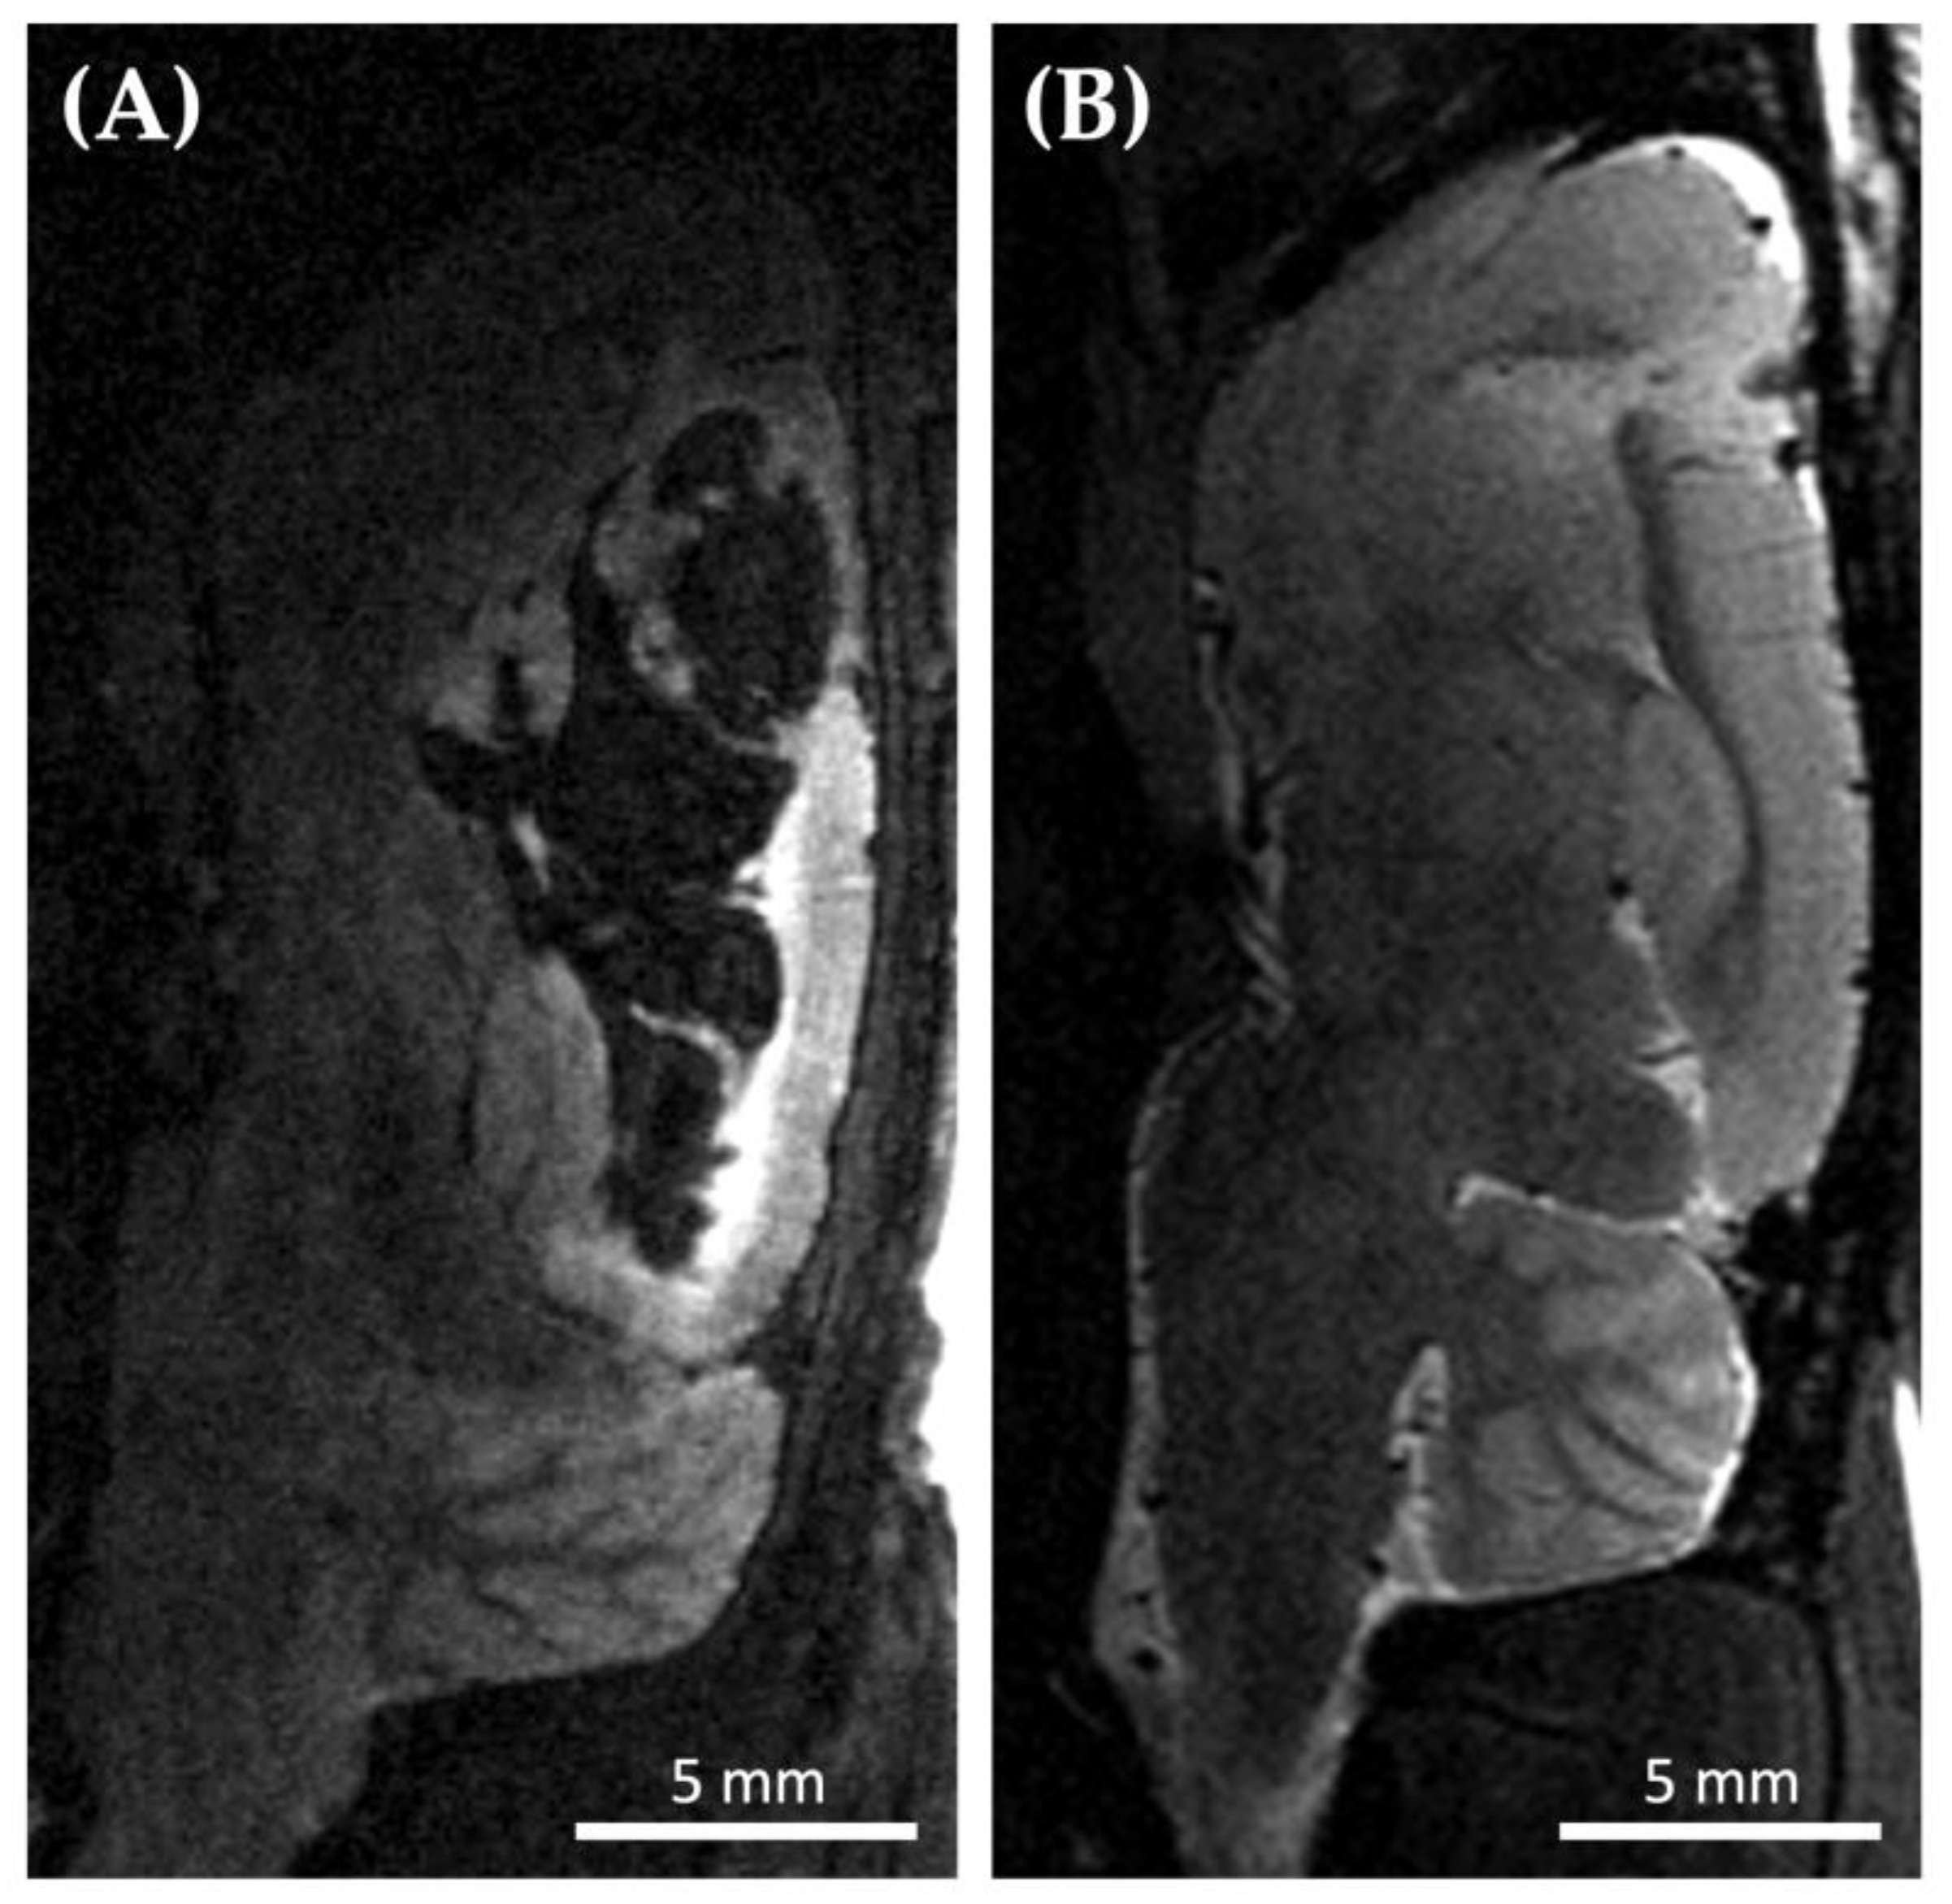

3.2.2. Standardized Inoculation Procedure

Cell cultivation and animal surgery often take place at different locations. This necessitates the transport of the cells to the place of inoculation. Transport of the cells (transported as a cell pellet to reduce shear stress of the cells to a minimum) taking place shortly before the tumor cell application appeared to be associated with late-onset (two to three weeks after inoculation) hemorrhages in the brain area of implantation. Three out of four Wistar rats developed significant tumor hemorrhages and only one revealed a marginal tumor hemorrhage (which is expectable during tumor progression). In contrast, if the cells were transported two to three days before the surgery and allowed to grow after transportation, the bleeding was significantly reduced (Figure 2). Only 1 out of 26 Wistar rats developed a moderate tumor hemorrhage—less pronounced than observed before. As expected, small tumor hemorrhages occurred in 11 out of 26 Wistar rats, and 14 animals showed no signs of tumor hemorrhage in the MRI. Hence, this strategy was used for all further experiments in our study, including all athymic animals.

Figure 2. Exemplary brain MRI (Magnetic Resonance Imaging) of two different Wistar rats 21 days after tumor cell inoculation. (A) Sagittal T2 weighted MRI of a Wistar rat 21 days after inoculation of C6 tumor cells revealing massive intracerebral hemorrhage (black). Cells were injected right after transfer to the implantation and imaging site (n = 4; 3 with significant tumor hemorrhage, 1 with marginal tumor hemorrhage as expected during tumor progression); (B) Sagittal T2 weighted MRI of a Wistar rat 21 days after inoculation of C6 cells that were injected 3 days after transfer (n = 26). None (n = 14) or mild (n = 11) hemorrhage occurred in twenty-five of the Wistar rats, while only one rat revealed a moderate tumor hemorrhage.